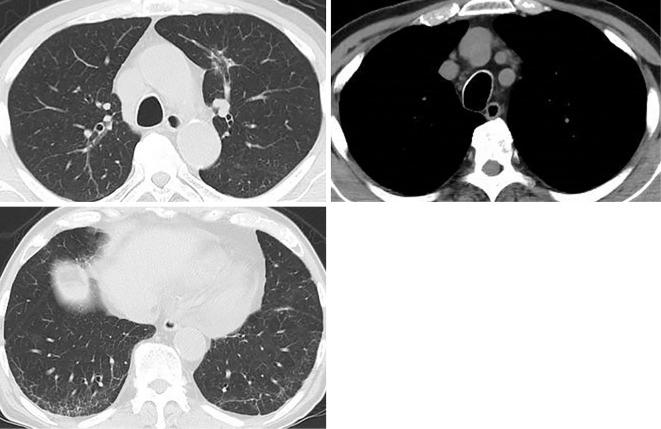

There are few cases describing the association of eosinophilia with hypercalcemia, and drug-induced eosinophilia with hypercalcemia has not been reported. A 74-year-old man had been diagnosed with asthma 4 months earlier. He was admitted due to eosinophilia with hypercalcemia. Chest computed tomography showed a nodule in the left lung and mediastinal lymphadenopathy. By obtaining a detailed medical history, clopidogrel was suspected as the prime cause of eosinophilia. After the discontinuation of clopidogrel, the eosinophilia with hypercalcemia, lung nodule and mediastinal lymphadenopathy improved. Clopidogrel-induced eosinophilia can potentially cause hypercalcemia. Obtaining a detailed clinical history is important in diagnosing the cause of eosinophilia.

目前仅有少数病例描述了嗜酸粒细胞增多与高钙血症之间的关联,而药物引起的嗜酸粒细胞增多与高钙血症尚未见报道。一名 74 岁男性在 4 个月前被诊断患有哮喘。他因嗜酸粒细胞增多伴高钙血症入院。胸部计算机断层扫描显示左肺结节和纵隔淋巴结病。通过详细询问病史,怀疑氯吡格雷是嗜酸粒细胞增多的主要原因。停用氯吡格雷后,嗜酸粒细胞增多伴高钙血症、肺结节和纵隔淋巴结病改善。氯吡格雷引起的嗜酸粒细胞增多可能导致高钙血症。详细的临床病史对于诊断嗜酸粒细胞增多的病因非常重要。